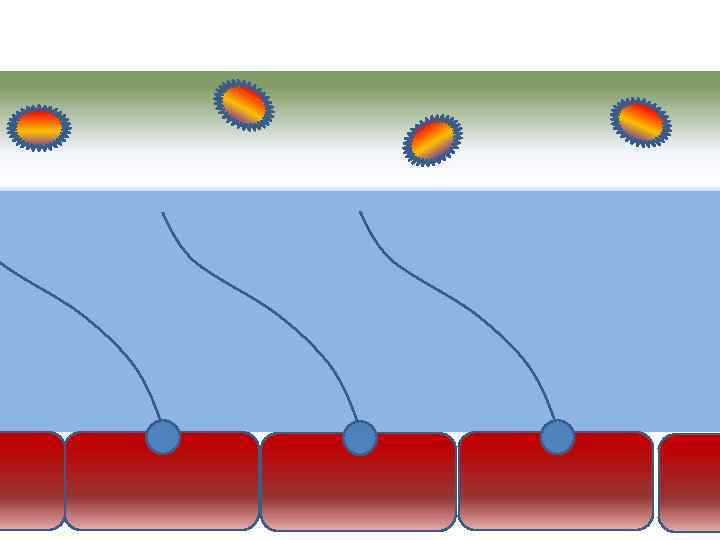

Факторы риска Недостаточное увлажнение дыхательной смеси ! Слизистая оболочка трахеи и бронхов обязательно должна быть укрыта секретом

Факторы риска Недостаточное увлажнение дыхательной смеси ! Слизистая оболочка трахеи и бронхов обязательно должна быть укрыта секретом

Факторы риска Недостаточное увлажнение дыхательной смеси • естественное удаление бактерий • состояние эпителия трахеи и бронхов

Факторы риска Недостаточное увлажнение дыхательной смеси • естественное удаление бактерий • состояние эпителия трахеи и бронхов

Оптимальное увлажнение 37°С, 44 мг/л Оптимальная влажность • Уменьшает время нахождения патогенной флоры в легком

Оптимальное увлажнение 37°С, 44 мг/л Оптимальная влажность • Уменьшает время нахождения патогенной флоры в легком

Механика движения воды из клеток вода П р о с в ет т р а х е и

Механика движения воды из клеток вода П р о с в ет т р а х е и

Движение клеток реснитчатого эпителия Движение вперед 1 – 3 Обратное движение 4 – 8

Движение клеток реснитчатого эпителия Движение вперед 1 – 3 Обратное движение 4 – 8

Оптимальное увлажнение Достаточная продукция слизи Хороший транспорт Экономит энергию и воду Защитная функция

Оптимальное увлажнение Достаточная продукция слизи Хороший транспорт Экономит энергию и воду Защитная функция

Механизм защиты легкого Слизь (зеленый цвет) нейтрализует и связывает патогенную флору(синий цвет) Слизь – это барьер между клетками и патогенной флорой Слизь – это транспортное средство

Механизм защиты легкого Слизь (зеленый цвет) нейтрализует и связывает патогенную флору(синий цвет) Слизь – это барьер между клетками и патогенной флорой Слизь – это транспортное средство